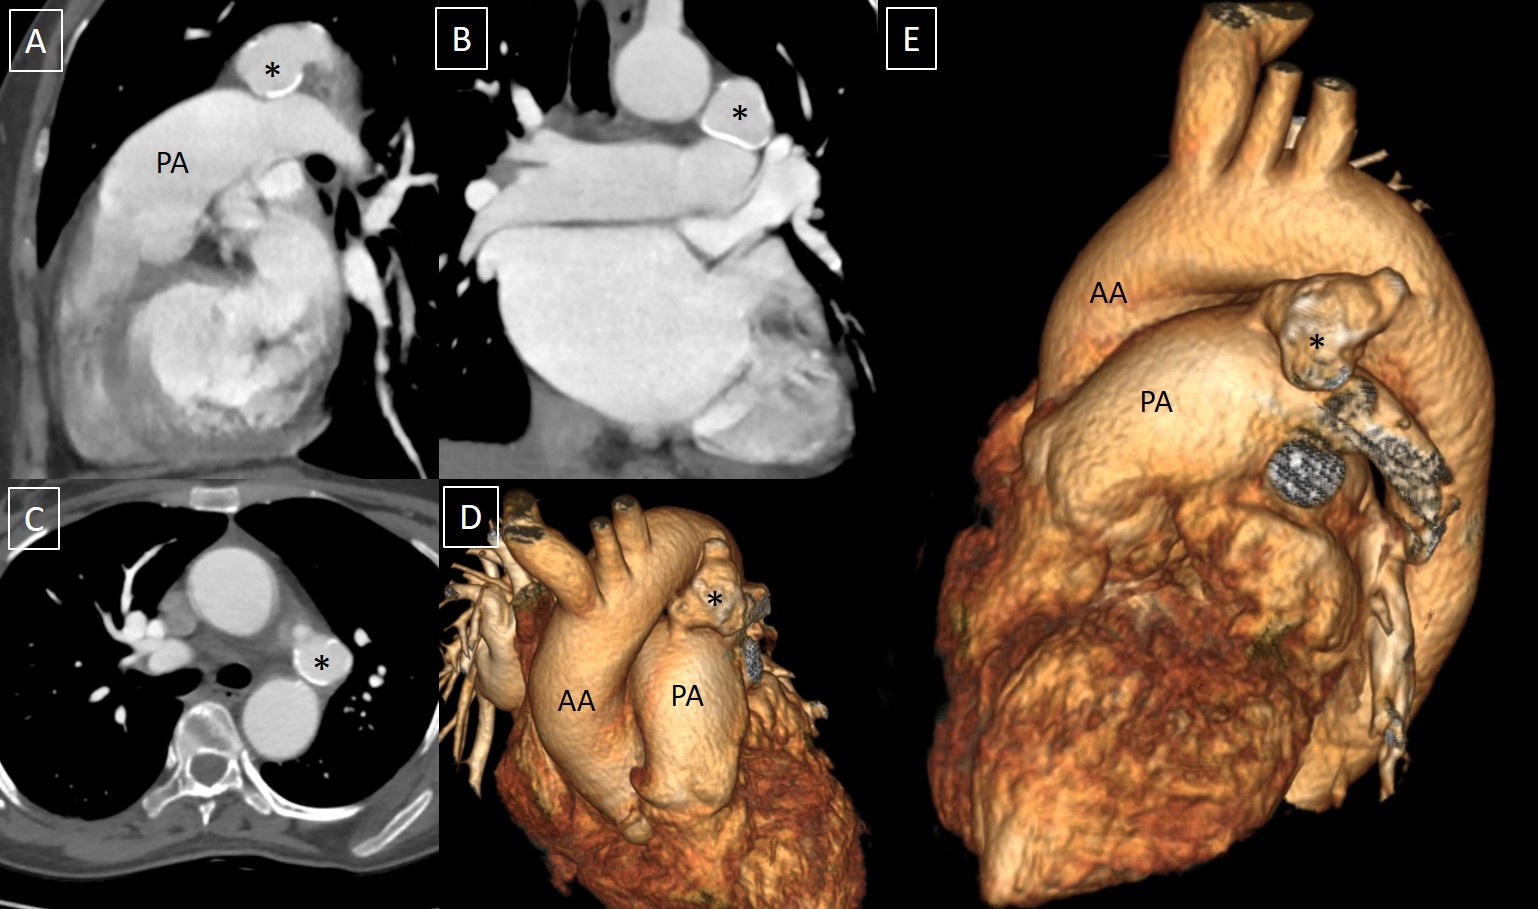

Computed tomography angiography revealed the presence of a PDA (measuring 8 mm at the PA end) with aneurysmal dilatation (measuring 25 x 21 mm) and peripheral calcification (Figure 1). No thrombus was seen within the aneurysmal sac, and no surrounding hematoma was seen. The aortic arch was left-sided with a normal branching pattern. No aortic coarctation, tortuosity, or dissection was seen.